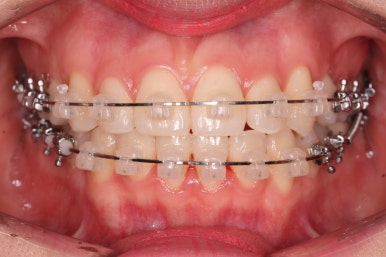

지그재그 방향으로 치열이 변해가는 중입니다.

이렇게 덧니가 가지런해지는데 1년도 채 안걸렸습니다.

마찬가지로 지그재그 방향으로 치열이 변해가는 모습입니다.

윗니들만 보면 이런 모습으로 변해가고 있습니다.